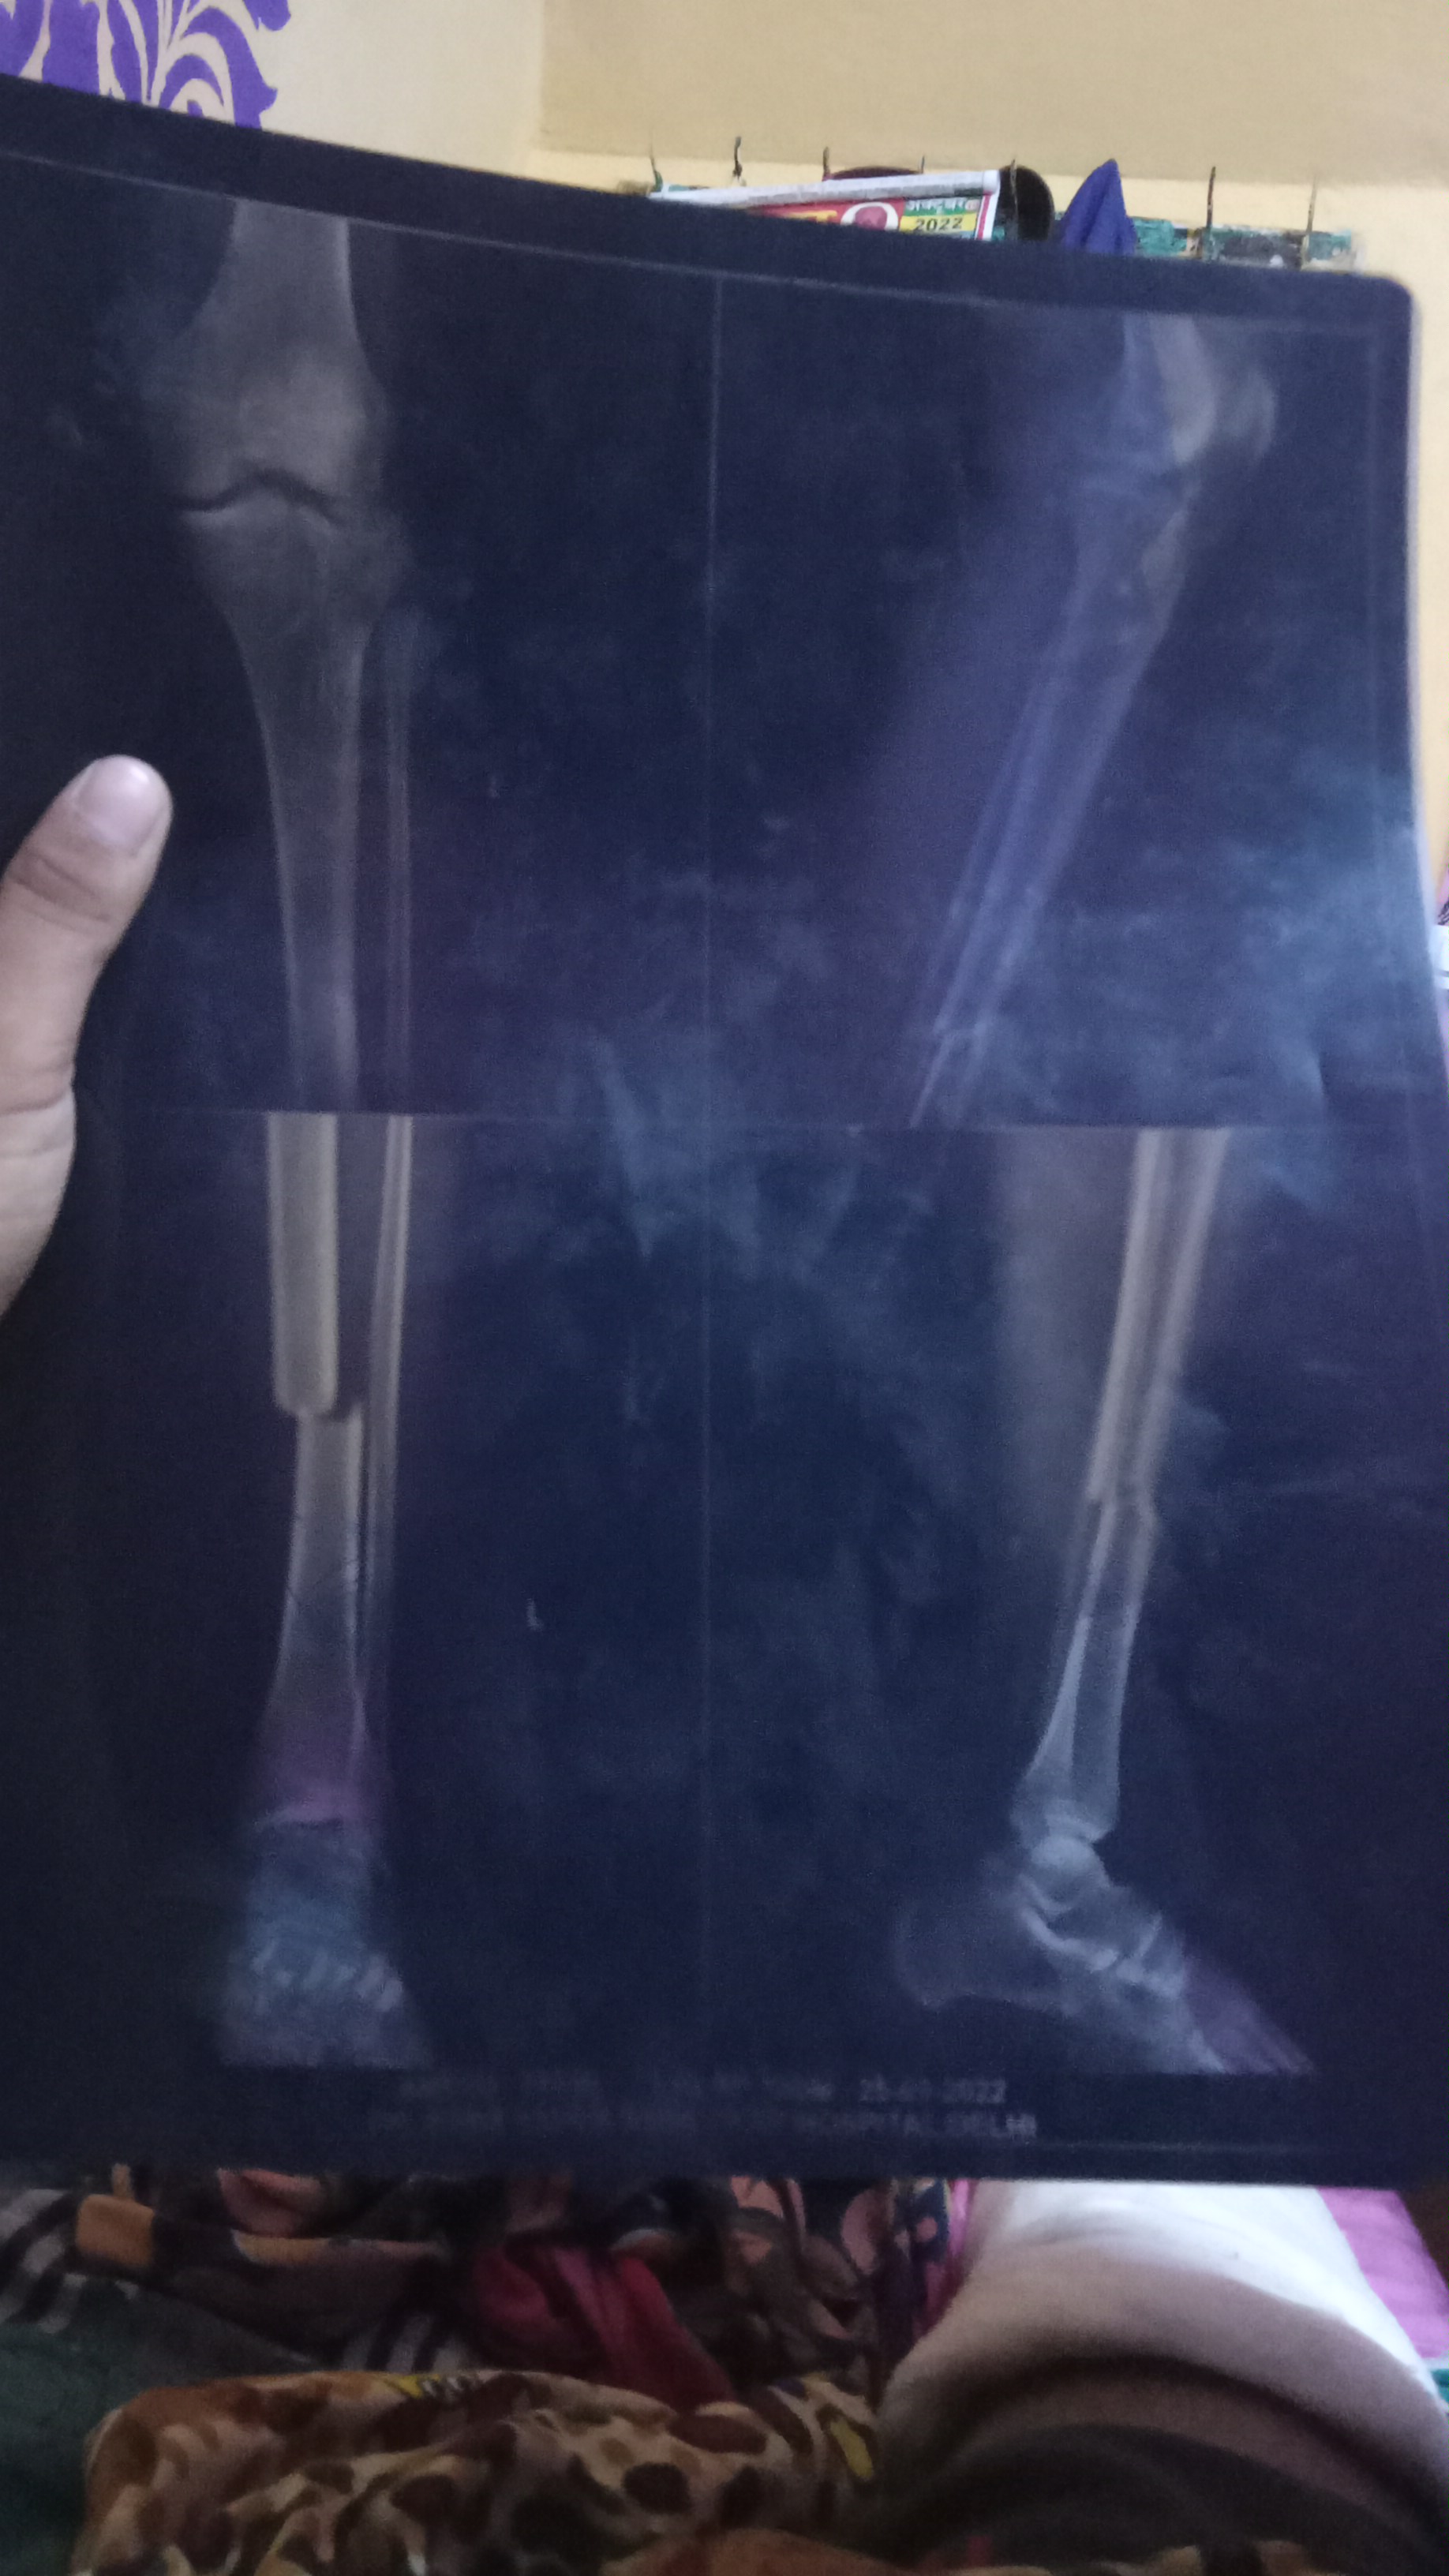

Meri tibia bone tut Gai h to kab tak thik hogi or  surgery hogi ya nhi doctor ji

Tibia bone tut Gai h to kitne manth Mai thik hogi or surgery hogi ya nhi

Tibia bone tut Gai h Meri to kitne din Mai thi ho Sakti h surgery hogi ya nhi